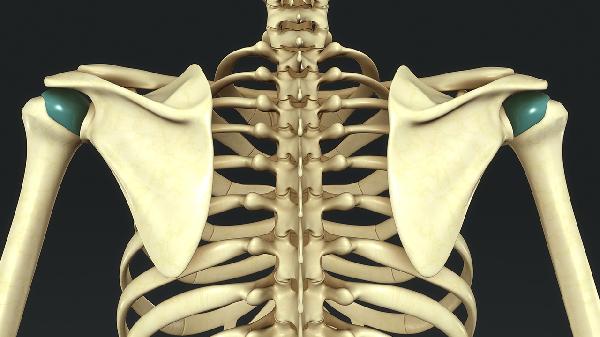

胸廓出口综合征有哪些表现

胸廓出口综合征主要表现为上肢疼痛、麻木、无力及血管受压症状。典型表现包括锁骨下动脉受压导致的手部发凉苍白、尺神经受压引发的小指麻木、臂丛神经受压引起的肩臂放射痛、静脉回流受阻导致的肢体肿胀、以及肌肉萎缩等晚期症状。